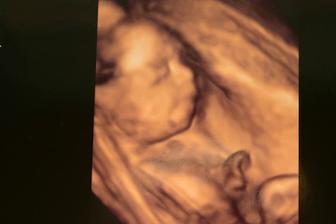

V lednu bude z Karlíka velký brácha 🙂

V den manželových narozenin jsem zjistila, že se naše rodinka rozroste - a termín porodu dle PM vychází na den mých narozenin. Ironií osudu je, že miminko bylo absolutně neplánované a cestičku si našlo samo 😀 O Karlíka jsme se snažili dlouhých 8 měsíců a další dítko jsme plánovali nejdříve příští rok v létě. Po počátečním šoku jsme moc šťastni za tuto variantu, než se každý měsíc trápit, že to zase nevyšlo.